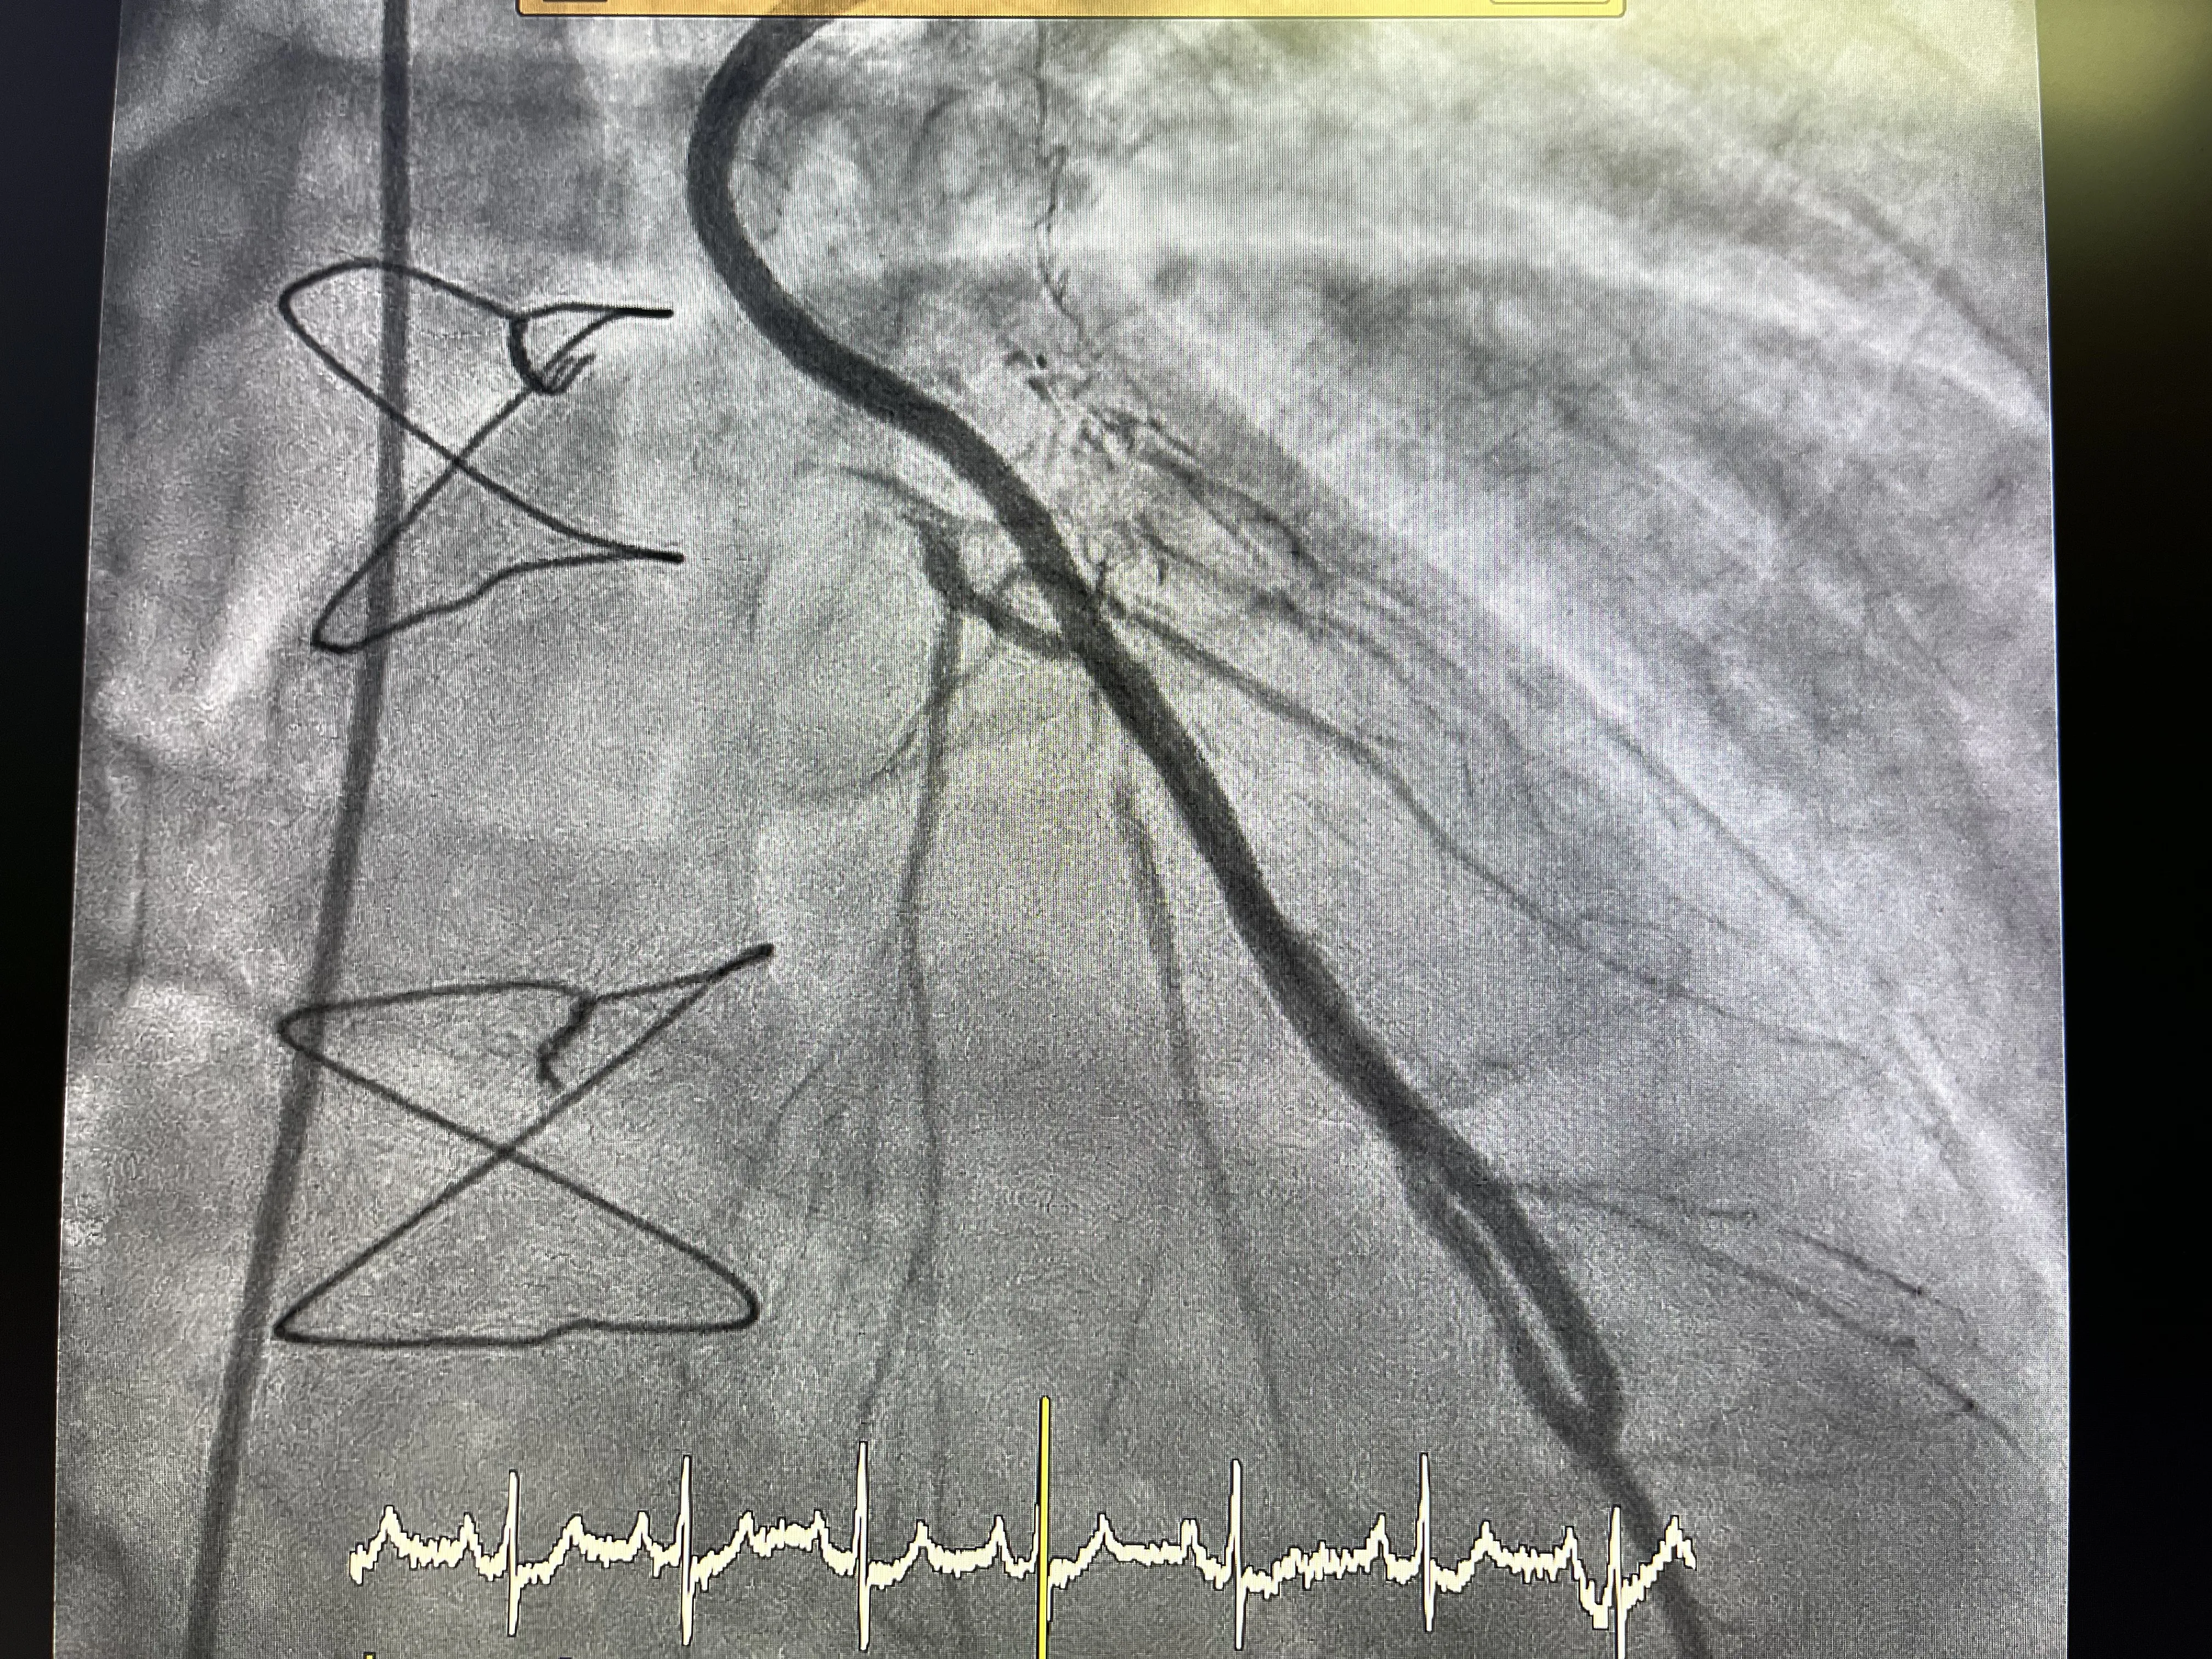

Estudio inicial: cateterismo por radial derecha

Para evaluar el estado actual del sistema cardiovascular del paciente, se realizó un cateterismo a través de la arteria radial derecha. Este procedimiento mínimamente invasivo permite obtener imágenes detalladas de las arterias coronarias y el bypass, proporcionando información crucial sobre la presencia de obstrucciones o estrechamientos que puedan estar contribuyendo a la angina inestable.

Evaluación del bypass en la angiografía

La angiografía realizada durante el cateterismo reveló que el bypass está en buen estado y cumple su función de irrigar la arteria descendente anterior. Este hallazgo es positivo, ya que indica que el bypass sigue siendo una vía efectiva para mantener el flujo sanguíneo al corazón, a pesar de las obstrucciones presentes en las arterias coronarias nativas.